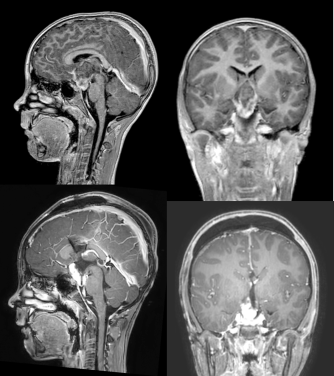

le troisième ventricule (V3) est une région distante, entourée de structures importantes : hypothalamus, voies visuelles, voies mnésiques, voie motrice, son abord est donc délicat, de même que le suivi post-opératoire.

les tumeurs du troisième ventricule entrainent le plus souvent une hydrocéphalie qui favorise l’abord trans-foraminal, celui-ci est donc le plus couramment utilisé; cependant aucun des abords possibles ne permet un contrôle d’ensemble du troisième ventricule.

la gestion de l’hydrocéphalie

avant l’intervention

il est parfois nécessaire de poser une dérivation ventriculaire externe en urgence ; le plus souvent un seul drain suffit à drainer les deux ventricules latéraux

il n’est que rarement possible de réaliser une venticulo-cisternostomie endoscopique, essentiellement pour les tumeurs très postérieures.

pendant l’intervention

la chirurgie du V3 permet le plus souvent de dégager les voies d’écoulement du LCS, en particulier l’aqueduc, et également de fenestrer le plancher du V3.

c’est donc une intervention qui peut être indiquée dans le but principal de traiter une hydrocéphalie rebelle (débulking).